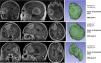

MétodosEstudio observacional retrospectivo unicéntrico de una cohorte de meningiomas sintomáticos intervenidos en el período comprendido entre enero de 2015 y diciembre de 2022. Mediante software de segmentación, para cada meningioma se calculó el denominado factor de superficie (FS), que es un parámetro objetivo que relaciona la superficie de una esfera (figura con la menor área para un volumen dado) de igual volumen que el tumor con la superficie real del tumor. Este cociente varía de 0 a 1, siendo 1 la máxima esfericidad posible. Dado que los meningiomas de forma irregular presentan una mayor superficie en relación con su volumen, su FS tiende a ser menor cuanto más irregular es el tumor. Se correlacionaron los FS con el grado histológico y se evaluó el poder predictivo del FS mediante curva ROC.

MethodsUnicentric retrospective observational study of a cohort of symptomatic meningiomas surgically removed in the time period between January 2015 and December 2022. Using specific segmentation software, the surface factor (SF) was calculated for each meningioma. SF is an objective parameter that compares the surface of a sphere (minimum surface area for a given volume) with the same volume of the tumor against the actual surface of the tumor. This ratio varies from 0 to 1, being 1 the maximum sphericity. Since irregularly-shaped meningiomas present proportionally greater surface area, the SF tends to decrease as irregularity increases. SF was correlated with WHO grade and its predictive power was estimated with ROC curve analysis.

ResultsA total of 176 patients (64.7% females) were included in the study; 120 WHO grade I (71.9%), 43 WHO grade II (25.7%) and 4 WHO grade III (2.4%). A statistically significant difference was found between the mean SF of WHO grade I and WHO grade II–III tumors (0.8651±0.049 versus 0.7081±0.105, p<0.0001). Globally, the SF correctly classified more than 90% of cases (area under ROC curve 0.940) with 93.3% sensibility and 80.9% specificity. A cutoff value of 0.79 yielded the maximum precision, with positive and negative predictive powers of 82.6% and 92.6%, respectively. Multivariate analysis yielded SF as an independent prognostic factor of WHO grade.

ResultadosSe incluyeron un total de 176 pacientes (64,7% mujeres); 120 grado OMS I (71,9%), 43 grado OMS II (25,7%) y 4 grado OMS III (2,4%). Se constató una diferencia significativa en el FS entre los meningiomas grado OMS I y los OMS II-III (0,8651±0,049 versus 0,7081±0,105, p<0,0001). Globalmente, el FS permitió clasificar correctamente a más del 90% de los pacientes (área bajo la curva ROC de 0,940), con una sensibilidad y especificidad del 93,3% y 80,9%, respectivamente. Un valor de corte de 0,79 proporcionó la máxima precisión para clasificar correctamente el grado histológico, con valores predictivos positivo y negativo del 82,6% y 92,6%, respectivamente. El análisis multivariante identificó el FS como factor pronóstico independiente del grado histológico.